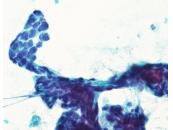

第40回日本臨床細胞学会九州連合会学会(大分)スライドカンファレンス症例2

種別:呼吸器

出題:今村 彰吾 独立行政法人国立病院機構九州がんセンター

| 年齢 | 50歳代 | 性別 | 女性 |

| 採取部位 | 気管支 | 採取方法 | 気管支鏡下生検捺印 |

既往歴 右頬粘膜癌(7年前)および肺転移(8年前)、歯肉癌(2か月前)

現病歴 右頬粘膜癌に対してニボルマブ投与中、PET-CTにて左気管支内に異常集積を指摘され、精査目的で当科紹介受診となった。

| 正解 | 5.間葉系腫瘍 |

▼選択肢及び投票結果

| 1.扁平上皮化生細胞 | 4件 | (3.8%) | |

| 2.扁平上皮癌 | 6件 | (5.7%) | |

| 4.非小細胞癌(肉腫様癌) | 35件 | (33.3%) | |

| 5.間葉系腫瘍 | 60件 | (57.1%) | |

| 投票総数 | 105件 | (100%) |